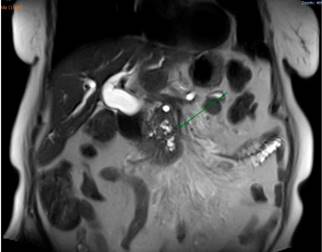

Se complementaron estudios con resonancia de abdomen simple que mostró una dilatación de la vía biliar intra- y extrahepática asociada con una masa pancreática localizada en la cabeza, con signos de compromiso de la raíz del mesenterio y lesión focal hepática en el sexto segmento de aspecto sospechoso (Figura 3).